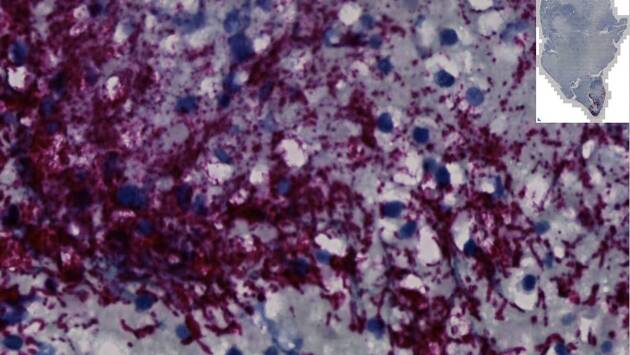

Изучив опухоли колоректального рака, удаленные у 200 пациентов, ученые измерили уровни Fusobacterium nucleatum — бактерии, которая, как известно, инфицирует опухоли. Примерно в 50 процентах случаев они обнаружили, что в опухолевой ткани чаще встречаются бактерии только определенного подтипа.

Проникающий в опухоли тип Fna C2 приобрел особые генетические особенности, которые позволяют ему перемещаться изо рта через желудок, противостоять желудочной кислоте, а затем расти в нижних отделах желудочно-кишечного тракта.

Пациенты с колоректальными опухолями, содержащими Fusobacterium nucleatum (примерно в 50 процентах случаев), имеют плохую выживаемость и худший прогноз по сравнению с пациентами без этого микроба. Таким образом, терапия и скрининг, нацеленные на эти микроорганизмы, помогут людям, которые подвергаются высокому риску развития более агрессивного колоректального рака.